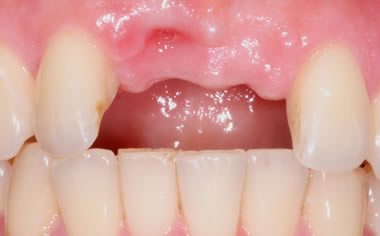

Missing upper front tooth replaced by dental implant and crown